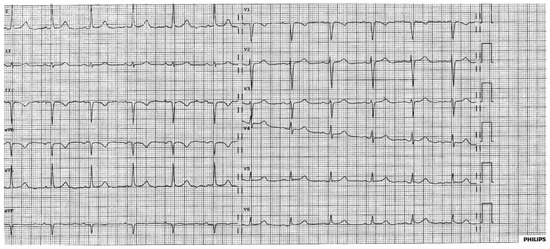

Interesting Images

A Strange ECG

by Mirdita Gaxherri and Jürg Schläpfer

Case presentation The 84-year-old patient, who lived abroad, was known to have ischaemic heart disease with an old posterobasal transmural infarction [...] Full article